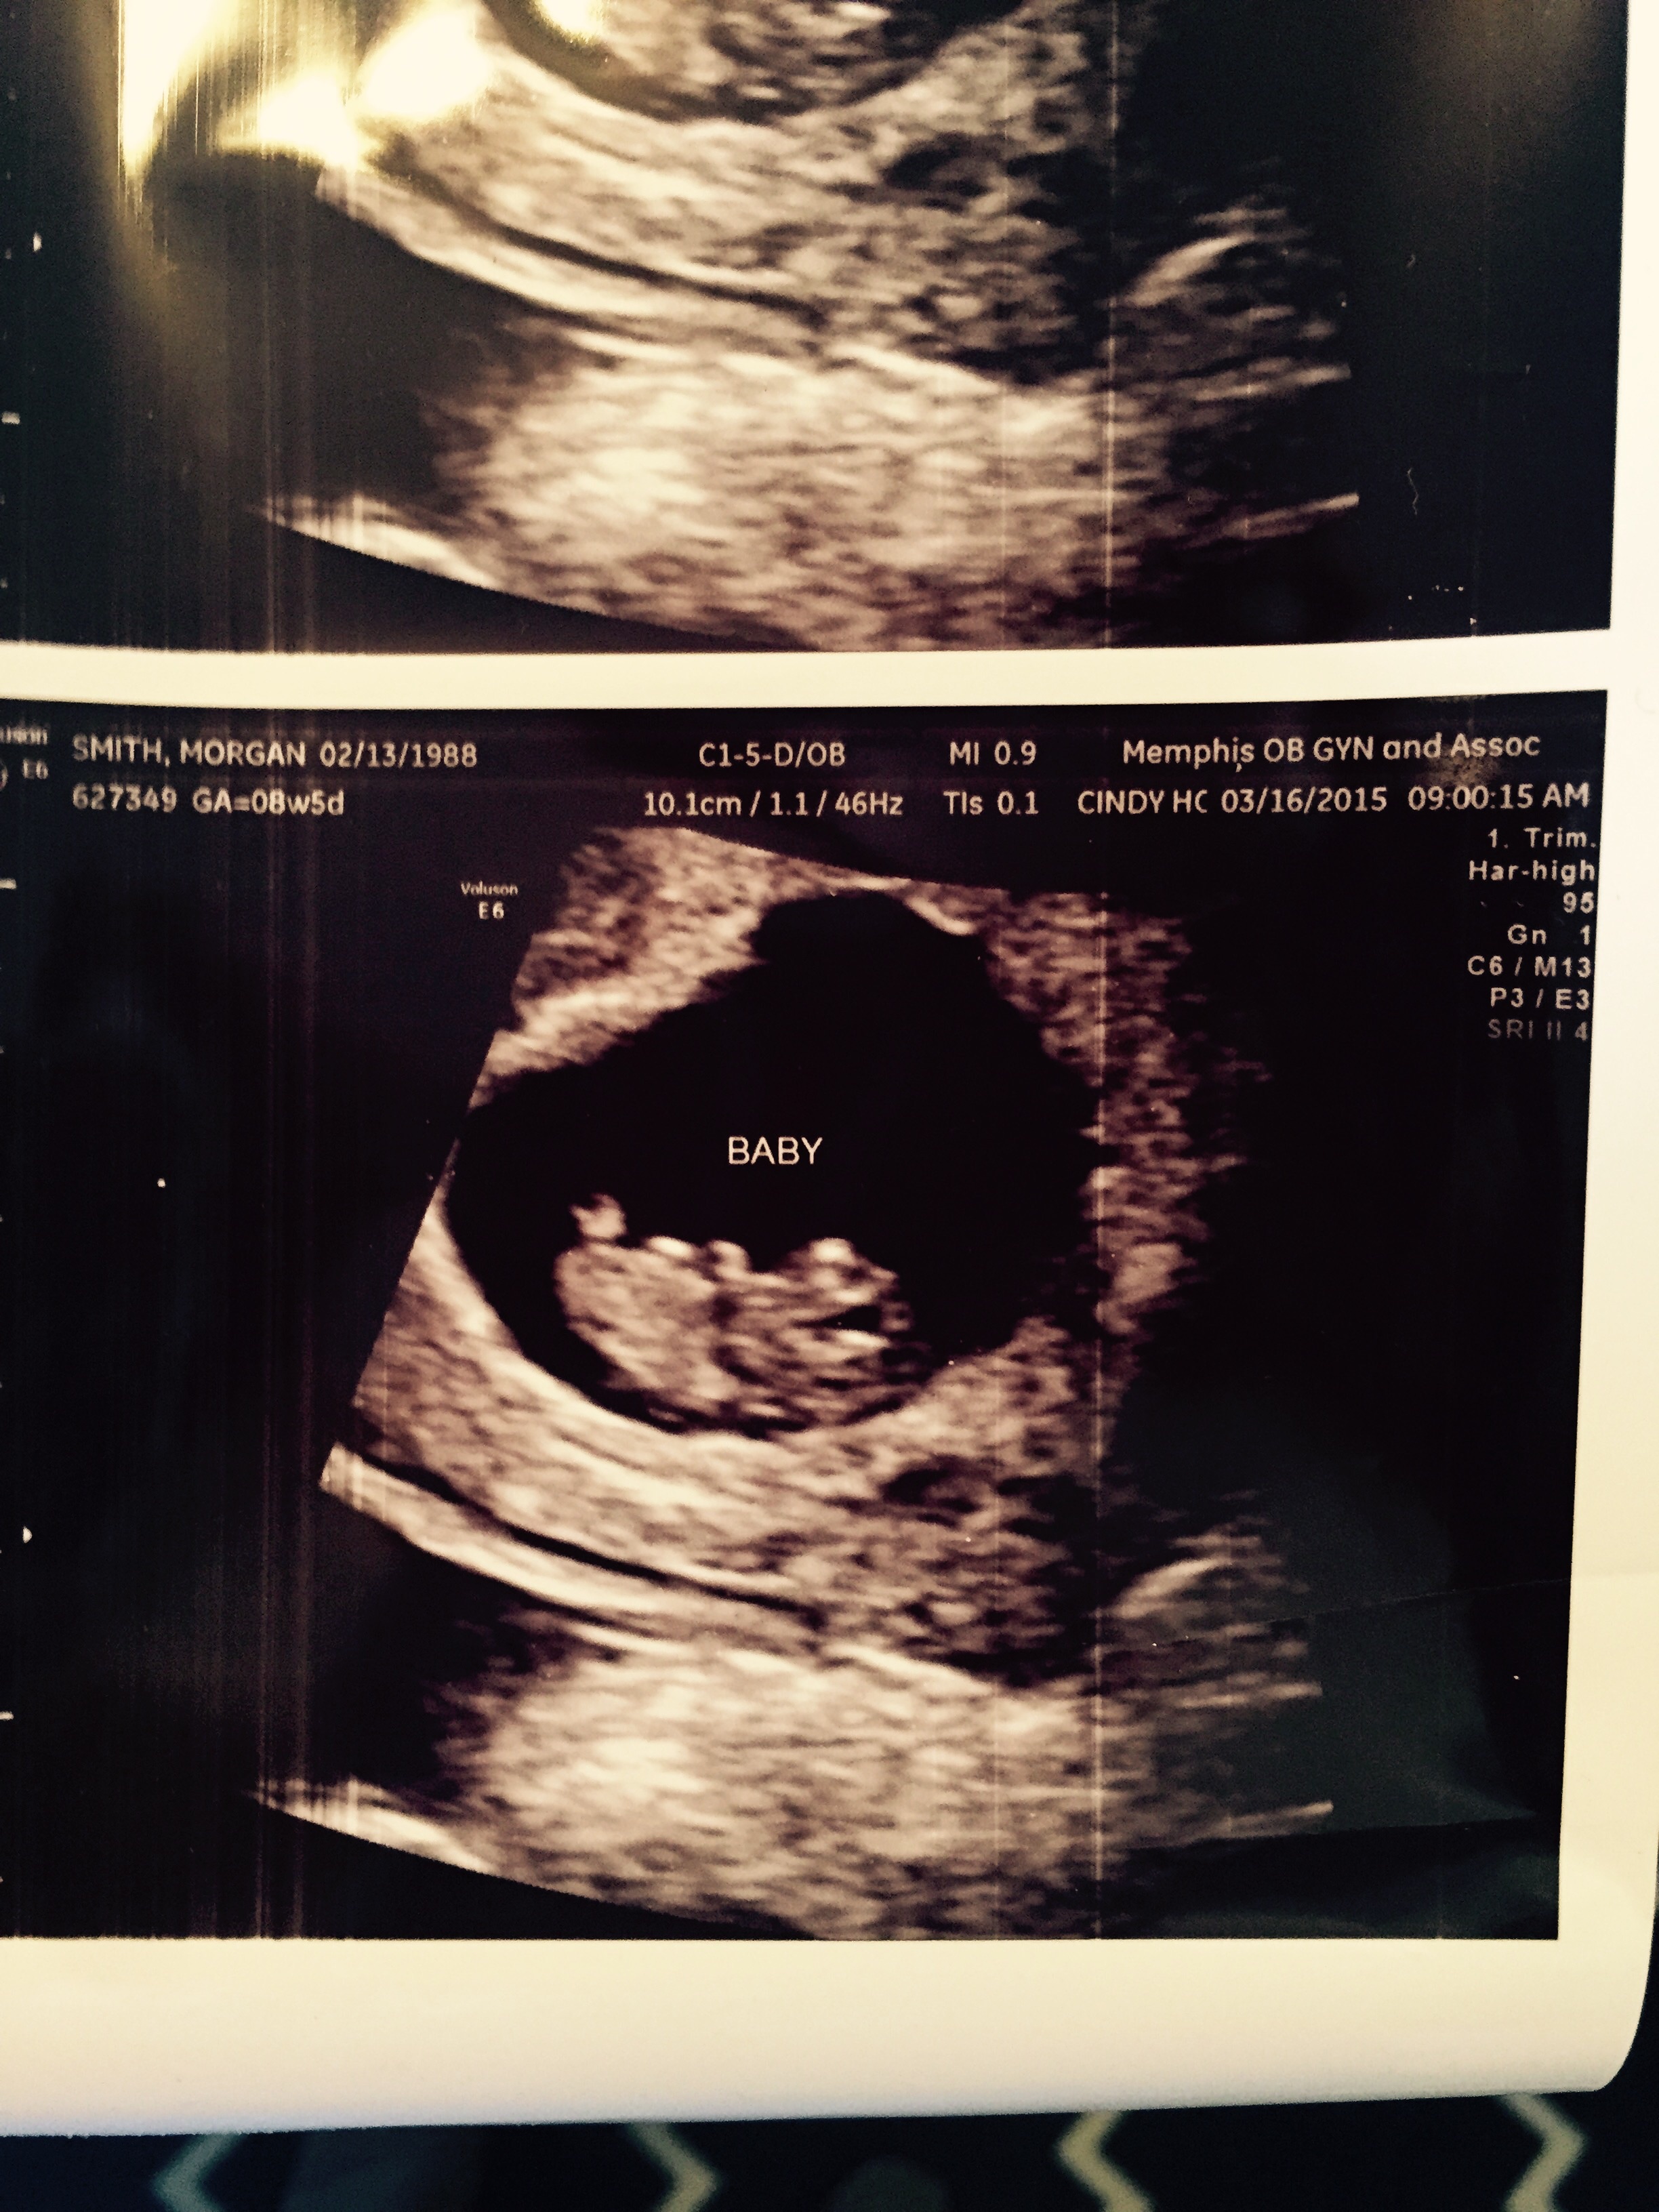

• I had my first US yesterday, at 8w5d. However, I know the exact date my LO was conceived, so technically 7w2d. My doc didn't do any "measurements", just went by LMP. Here's the pic I got in hopes it can help you mentally prepare. We got to see a little movement and hear an awesome HB!